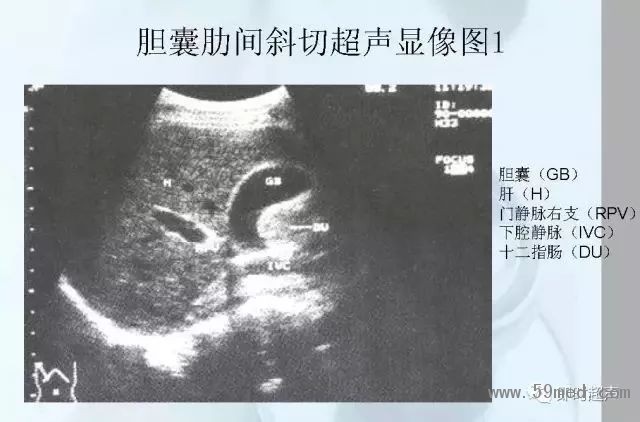

新聞中心 收藏!正常B超解剖圖譜,超實用!